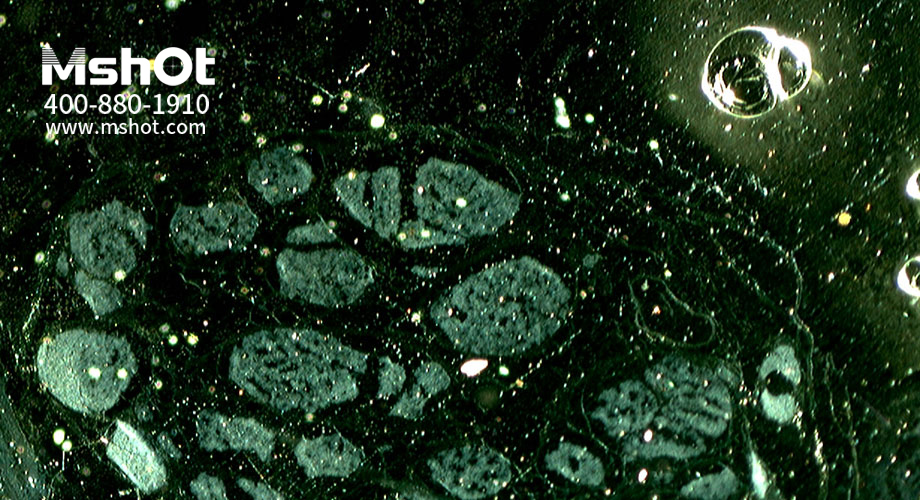

神經(jīng)纖維切片顯微圖片。 (操作提示:點(diǎn)擊圖片或使用鍵盤上的方向鍵來轉(zhuǎn)換要查看的圖片)